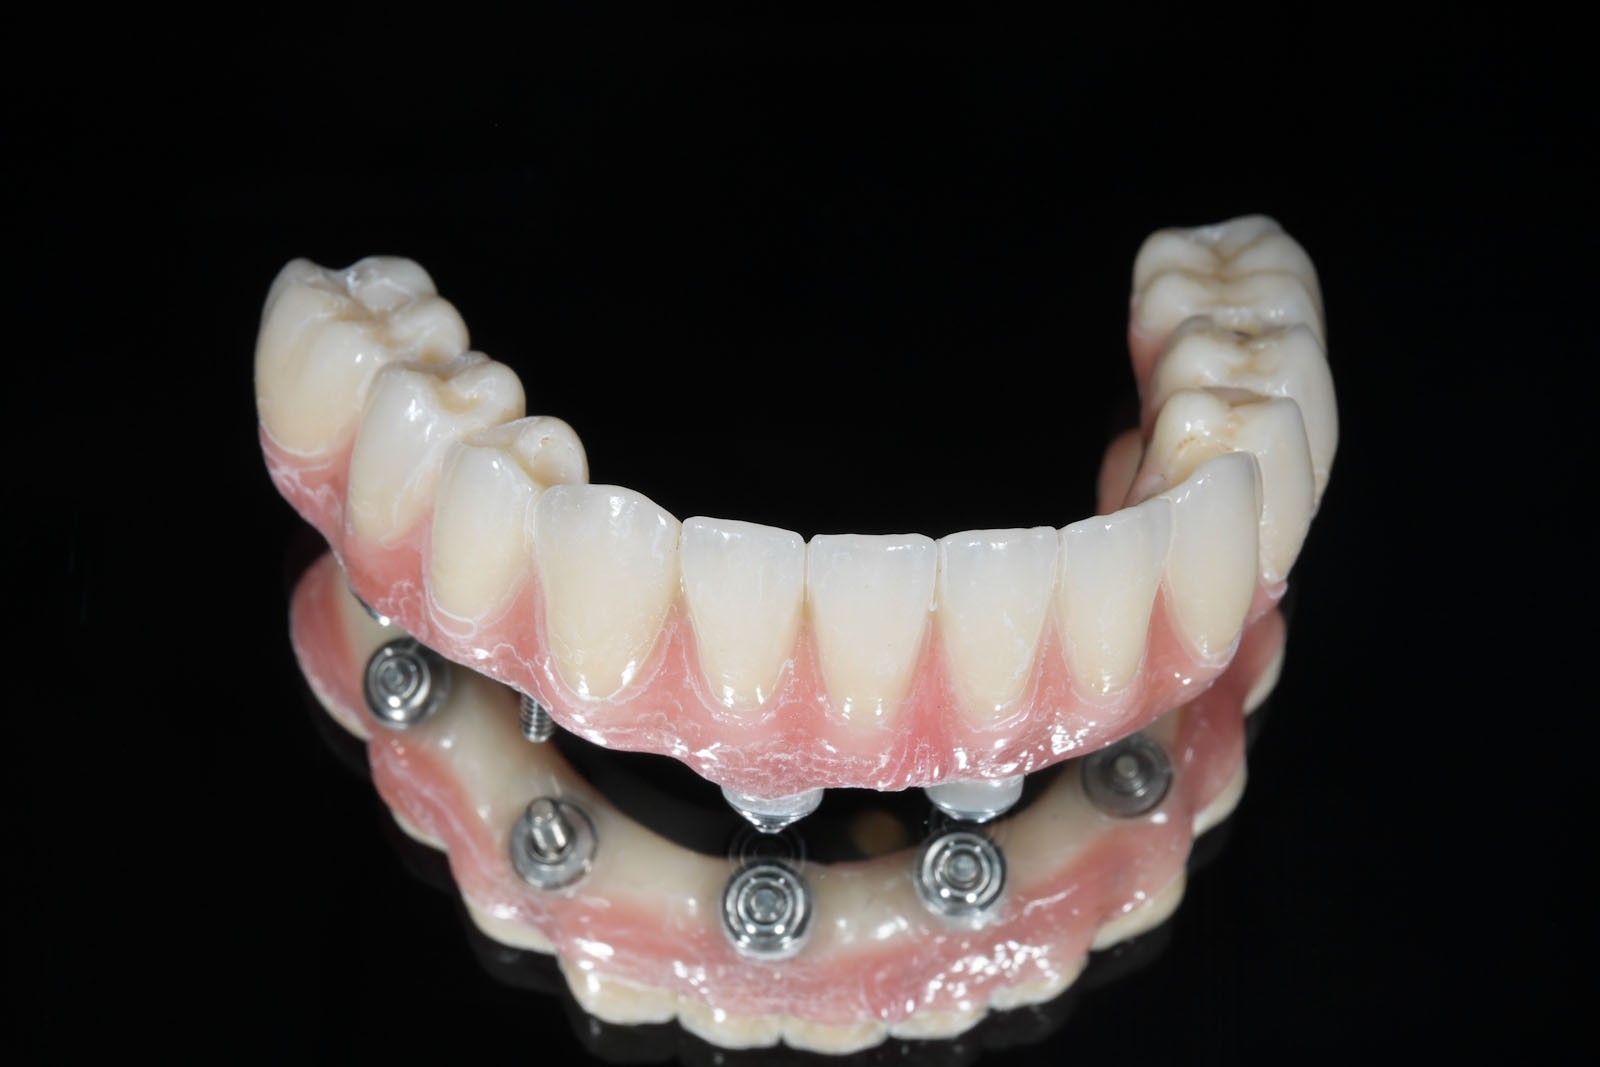

Są pośrednim rozwiązaniem pomiędzy ruchomymi protezami osiadającymi a na stałe montowanymi na implantach mostami. To również ruchome protezy o zredukowanej płycie, których zasada działania polega na tym, że są częściowo wsparte na implantach.

Zazwyczaj umocowuje je do podłoża od 2 do 4 wszczepionych implantów, dla których optymalną pozycją jest przednia część wyrostka zębodołowego szczęk lub żuchwy.

Za stabilizację pomiędzy płytą protezy nakładowej a wszczepami odpowiedzialne są różnego typu odpowiadające sobie elementy retencyjne. Z jednej strony przytwierdzone są do szyjek implantów, z drugiej – do płyty protezy Overdenture.

ROZWIĄZANIA PROTETYCZNE ALL-ON-4

Na implantach wszczepionych zgodnie z protokołem all-on-4 możliwe są do wykonania stabilne mosty, jak również ruchome protezy typu nakładowego. Uproszczenie i optymalizacja rozwiązań protetycznych możliwa jest dzięki zastosowaniu kątowych łączników typu MultiUnit (17°, 30°), które po przykręceniu do pochylonych implantów umożliwiają łatwe mocowanie mostu i obsługę serwisową pacjenta.